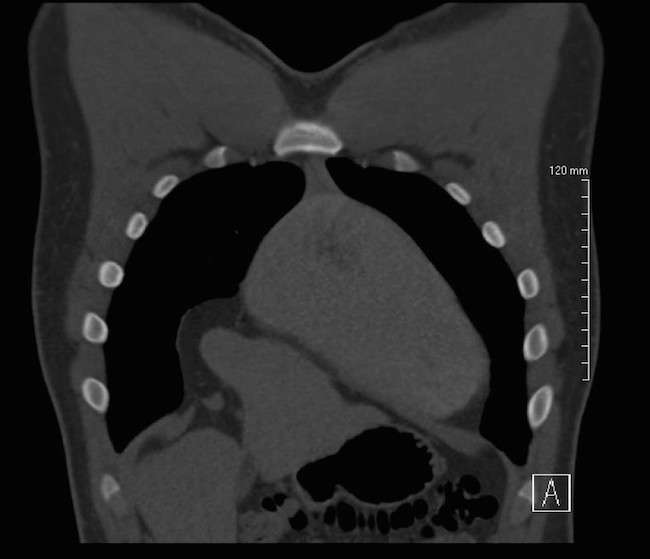

A 19 year old previously healthy male, NCAA defensive end, presents with four months of intermittent, non-exertional, midsternal chest pain and pressure. The pain is described as an episodic band like pressure radiating across the epigastrium. At maximum the pain is rated four out of ten and is completely relieved with holding a deep inspiration. There are no other mitigating or exacerbating factors. There are no other associated symptoms. This has never happened previously. Initial workup in the emergency department with chest radiograph revealed a right cardiophrenic angle mass. Electrocardiogram, complete blood count, comprehensive metabolic panel, lipase and troponin were within normal limits. Computed tomography scan revealed intrathoracic herniation of the left lobe of the liver through a large Foramen of Morgagni hernia over the right aspect of the heart. The patient obtained cardiothoracic surgery consultation and opted to forego surgical intervention while symptoms remained mild to moderate. The patient successfully returned to play and completed a full season as an NCAA defensive end without complication. The patient has another year of eligibility and plans to complete his collegiate career without surgery if symptoms remain stable.